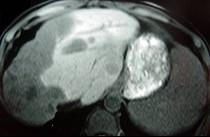

问题 女性,72岁,腹胀不适1年,加重伴恶心、呕吐、乏力1个月,影像检查如图,最可能的诊断为 ( )

选项 A.肝硬化腹水 B.原发性肝癌 C.肝血管瘤 D.巴-希综合征 E.局灶脂肪肝

答案 D